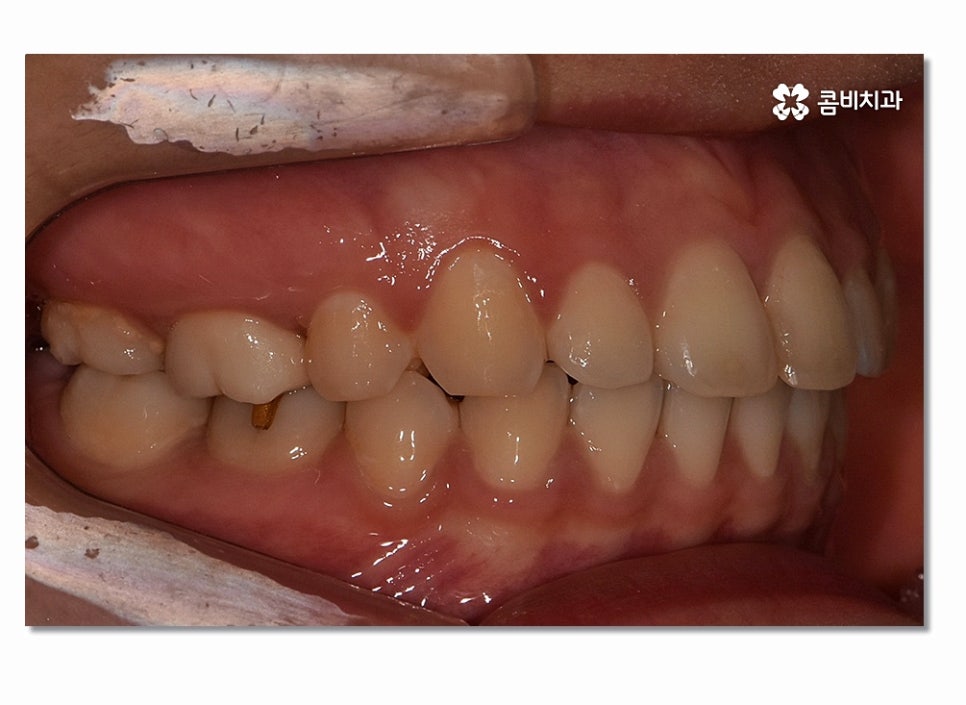

치아의 심미성은 앞모습뿐 아니라 측면 그리고 자신의 얼굴과

자연스럽게 어울리는지 등을 함께 살펴야 하기 때문에

얼굴 변화를 기대하면서 치아교정을 결심하시는 분들도 많이 있는데요.

위 사진을 보시면 치아교정 과정을 통해서 치열의 가지런함은 물론이며

측면에서 보더라도 돌출입이 많이 개선된 것을 느낄 수 있을 거예요.